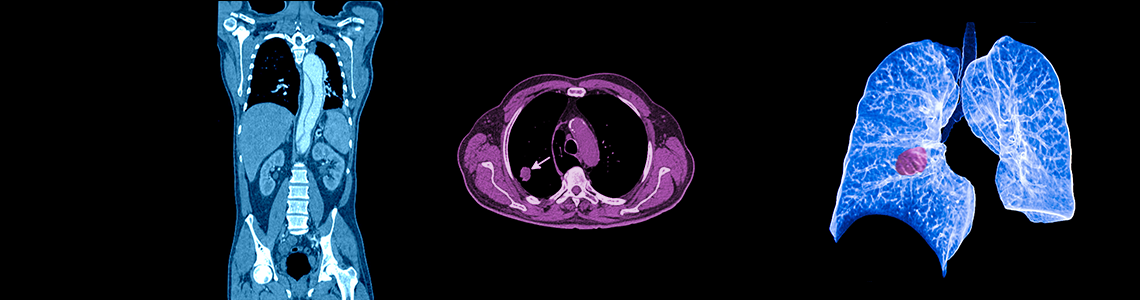

Computertomographie (CT), Spiral CT

Bildgebendes Verfahren in der Radiologie

Was ist eine Computertomographie? Warum eine Computertomographie?

Die Computertomographie wurde 1972 von dem Physiker Cormack und Ingenieur Hounsfield entwickelt. Es handelt sich um ein spezielles Röntgenschnittbildverfahren, das im Millimeterbereich Querschnittbilder unseres Körper entstehen lässt.

Die Röntgenröhre erzeugt einen fächerförmigen Röntgenstrahl, der in dem Gewebe unseres Körpers unterschiedlich geschwächt wird. Detektoren messen die Strahlenintensität und wandeln diese in elektrische Signale um, die in einem Rechenverfahren das Röntgenbild und Querschnittsbild des Körpers darstellen.

Es eröffnen sich Möglichkeiten der 3D-, MPR- (Multiplanare Rekonstruktionen), MIP- (Maximale Intensitätsprojektionen Technik), SSD- (Shaded Surface Display) Technik mit Oberflächendarstellung.

Die Schichtdicke schwankt zwischen 1 mm und 20 mm.

Durch die moderne Spiraltechnik, die wir anwenden, können in wenigen Sekunden Querschnittsbilder der Lunge, des Kopfes, der Wirbelsäule, der Gelenke, des Abdomens und des kleinen Beckens erzeugt werden.

Es handelt sich um ein „Arbeitspferd der Radiologie“ und dient zur Feststellung von Blutungen, Gehirntumoren, Schädelfrakturen, Knochenfrakturen, Tumoren im Brust-, Bauchraum, Entzündungen der Leber der Nieren, Gefäßtumoren, Gefäßerweiterungen (Aneurysma), Lymphknotenerkrankungen (M. Hodgkin), Metastasen und anderen Gefäßerkrankungen. Besonders gut sieht man Verkalkungen.

Die verbesserte Volumenabdeckung und höhere Auflösung des Mehrzeilen-Computertomographen erlaubt innerhalb von Sekunden den Blick in Kopf, Hals, Brust, Becken, Wirbelsäule, Gelenke und sonstigen Körperteile. Mit Hilfe des Geräts kann man quasi wie mit einem U-Boot durch Darm und Gefäße fahren. Auch können Kontrastmittel optimaler zum Einsatz kommen und Verletzungen oder Störungen von Organen und Gliedern einfacher diagnostiziert werden. Dabei erfolgt die Darstellung trotz des enormen technischen Fortschritts der modernen Geräte weiterhin in Schwarz-Weiß, weil gegenüber Farbe eindeutiger und schneller krankhafte Veränderungen erkannt werden können.